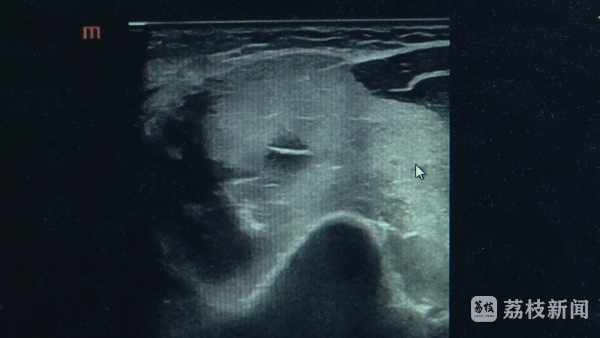

南京市中西医结合医院超声科副主任医师李亚洲介绍,进行超声检查的时候就发现,肩部上肢的肌肉广泛地肿胀,回声纹理模糊不清,和正常的一看就不一样,因为它的范围比较广,B超看了之后就怀疑这个病横纹肌溶解综合征。